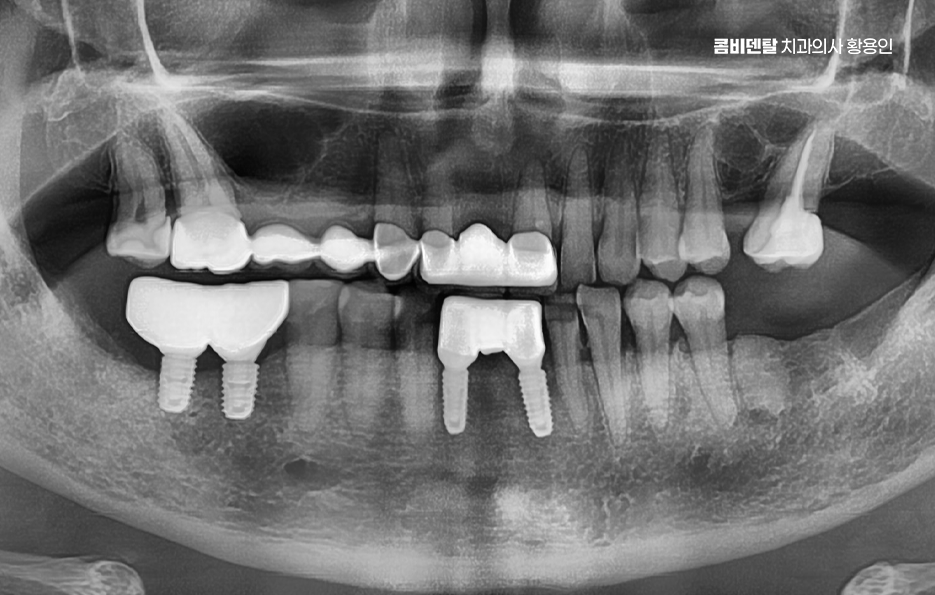

임플란트의 장점 이 골유착이 완성된 이후에는 그 위에 기둥을 세우고, 마지막으로 보철물을 씌우게 되는데 이렇게 되면 겉에서 보기엔 자연치아와 거의 차이가 없으며 심지어 기능적으로도 자연치아와 유사한 수준의 저작력이 가능해지며 다시 말해 뿌리부터 머리까지 인공치아를 만드는 건데 ‘뼈에 심는’ 것이기 때문에 더 안정적이고 오래 쓸 수 있는 치료인 거예요.

이러한 치료 원리를 토대로 임플란트의 장점을 정리해보면 첫 번째로 큰 장점은 주변 치아에 손상을 주지 않는다는 점으로 예전에는 치아를 하나 잃으면 양 옆의 치아를 깎아서 브릿지를 씌우는 방식이었어요. 문제는 건강한 치아까지 손상시켜야 한다는 점이었고 게다가 브릿지 아래는 관리가 어렵다 보니 2차 충치가 생기기 쉬워서 결국 더 많은 치아를 잃게 되는 경우가 많았던 것인데 임플란트는 해당 부위만 단독으로 치료하기 때문에 주변 치아는 그대로 두고, 본인 치아처럼 기능하게 할 수 있었어요.

또한 임플란트는 잇몸 뼈에 고정돼 있어서 씹는 힘이 자연치아의 80~90%에 가까울 정도로 강하고, 사용하면서도 불편함이 거의 없다는 장점이 있는데 틀니와는 비교가 어려운 씹는 힘을 복원할 수 있고 개별 치아를 대상으로 치료가 가능하다는 임플란트의 장점은 현재 임플란트가 도입된 이후에 빠르게 대중화된 대표적인 이유라고도 볼 수 있어요